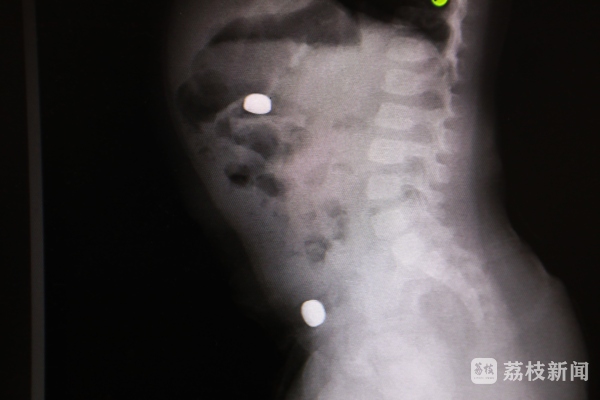

当晚,小天突然出现恶心、呕吐,还伴有腹痛,家人立即带其就医。医生查体发现,小天腹部发胀,有压痛和反跳痛,怀疑可能是异物所致。“做了腹部平片,发现腹腔里有两个光亮的影子。询问病史,家长高度怀疑是家里的纽扣电池被孩子吞了。”淮安市妇幼保健院小儿外科主治医师张岩说。

纽扣电池是低龄幼儿容易误吞误食的常见异物之一,同时它也是最具危险性的异物之一。电池中含有腐蚀性物质,如果电池在短时间内顺利排出还没有大的问题,一旦不慎卡在儿童身体内,数个小时后内容物就会不断流出,可能会造成消化道穿孔、引发腹膜炎、败血症,严重时甚至危及生命。由于不能明确电池误吞的时间,必须立即手术取出,避免危害升级。“术中发现,一颗电池位于十二指肠,另一颗位于小肠,两处都出现了发黑坏死的前期症状,再拖延下去,消化道就要穿孔了。取出来的电池已经有破损并且发生了泄露。”张岩说。